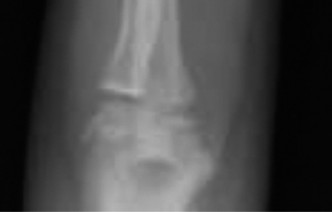

The intra-operative posteroanterior fluoroscopic view demonstrated excellent restoration of the radial length and correction of the coronal plane alignment. The fracture fragments appeared anatomically apposed.

The intra-operative lateral fluoroscopic view confirmed successful reduction of the dorsal displacement and complete correction of the apex volar angulation. The volar cortical continuity was restored, and the dorsal periosteal hinge appeared to be holding the reduction in an anatomical position.

Percutaneous Pinning Construct

Despite the excellent fluoroscopic appearance of the closed reduction, the initial displacement parameters (75% translation) indicated a highly unstable fracture pattern. To prevent secondary loss of reduction, percutaneous pinning was performed.

Smooth 0.062-inch (1.6 mm) Kirschner wires (K-wires) were selected. Smooth wires are preferred over threaded wires in pediatric trauma as they are less likely to cause permanent damage to the physeal chondrocytes during insertion and removal.

A standard crossed-pin configuration was utilized to provide maximum biomechanical stability against both bending and torsional forces.

Clinical & Radiographic Imaging